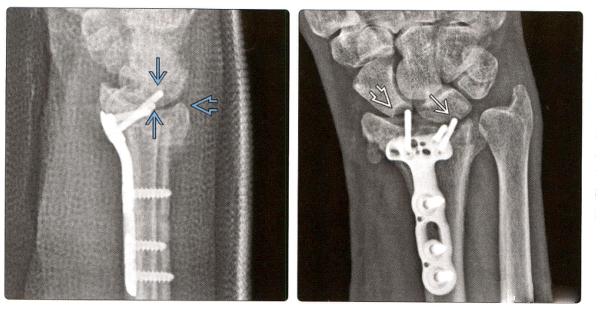

5. (Фото слева) Боковая рентгенограмма после установки ладонной пластины при переломе дистального отдела лучевой кости показывает, что 2 дистальных винта доходят до лучезапястного сустава. Нормальный наклон ладоней до сих пор не восстановлен.

(Справа) Перелом зажил через 6 месяцев, но неправильно расположенный винт задел и изменил форму проксимального отдела ладьевидной кости, возможно, повредив ладьевидно-полулунную связку. Полулунная кость также может быть поражена и повреждена.